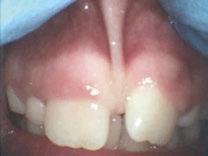

Figure 1: Preoperative periapical radiograph of tooth No. 30 with a large radiolucent lesion approximating the distal pulpal horn and a smaller radiolucent lesion closer to the mesial marginal ridge Figure 3: Conservative removal of all carious dentin on all axial walls and pulpal floor. No clinical pulpal exposure noted, but likely very close to distal buccal pulp horn Figure 2: Large active carious lesion involving the entire distal buccal cusp and surrounding aspect of tooth No. 30. Smaller Class VI lesion located on the mesial lingual cusp on No. 30 Figure 4: Placement and curing of two separate thin layers of NeoLINER over the dentin. Image depicts the NeoLINER following the indirect pulp cap of tooth No. 30